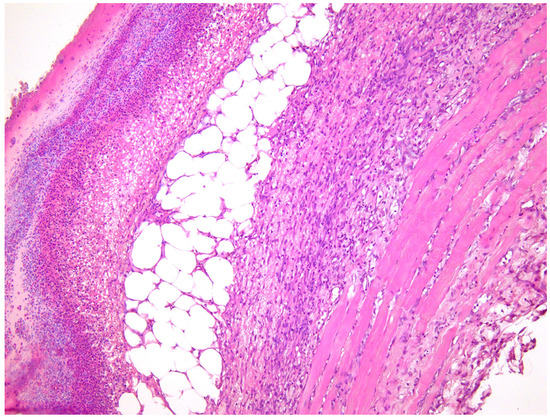

—fibrin clot,

—granulation tissue,

—fibrotic tissue,

—adipose tissue.